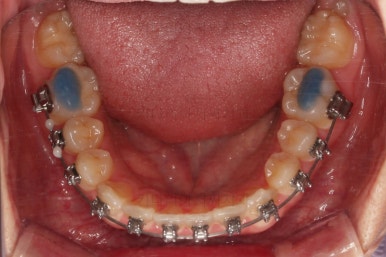

부산치아교정치과 초진 시 입안의 모습입니다.

앞니쪽이 위아래 모두 삐뚠 상태였고요.

왼쪽은 덧니로 툭 튀어나가 있고, 상대적으로 작은 앞니는 안으로 말려 들어가 아랫니와도 거꾸로 물리는 상태였습니다.